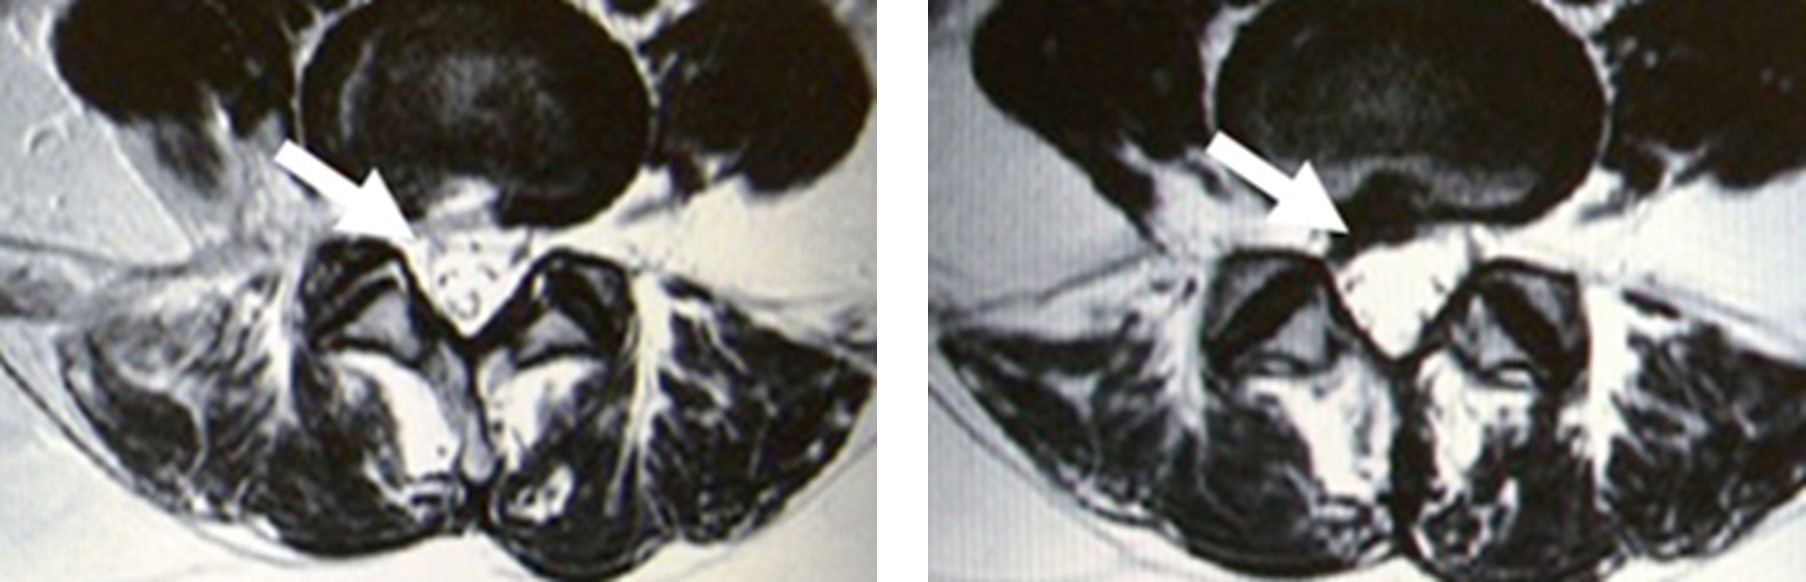

手術前の黒く映るヘルニア(左:白矢印)が手術後(右:白矢印)完全に摘出されています。